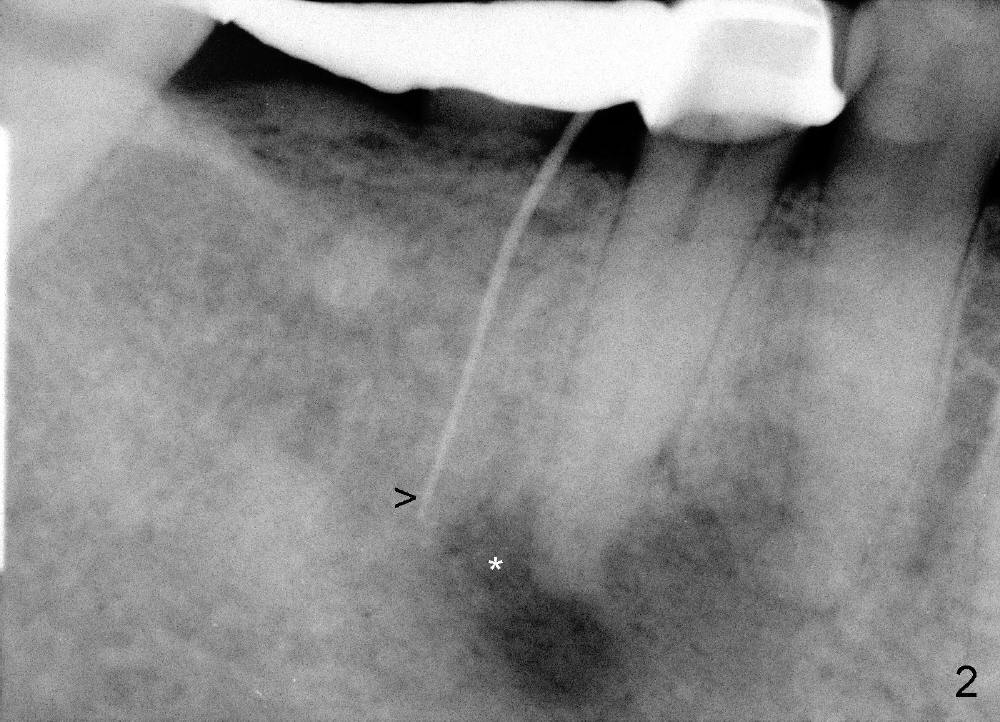

A 49-year-old lady cannot chew with the lower right bridge (Fig.1: from the 2nd premolar (5) to the third molar (8)). Insertion of gutta percha (Fig.2 >) points to the apical radiolucency of the anterior abutment (*). The bridge is sectioned between the pontic of 2nd molar and the retainer of the posterior abutment. The anterior segment of the bridge falls out. The anterior abutment is non-salvageable due to severe 2nd caries (Fig.3 (5) part of panaramic X-ray). The yellow lines denote the inferior alveolar nerve. In brief, the apex of the affected tooth is most likely closely associated with the mental loop.